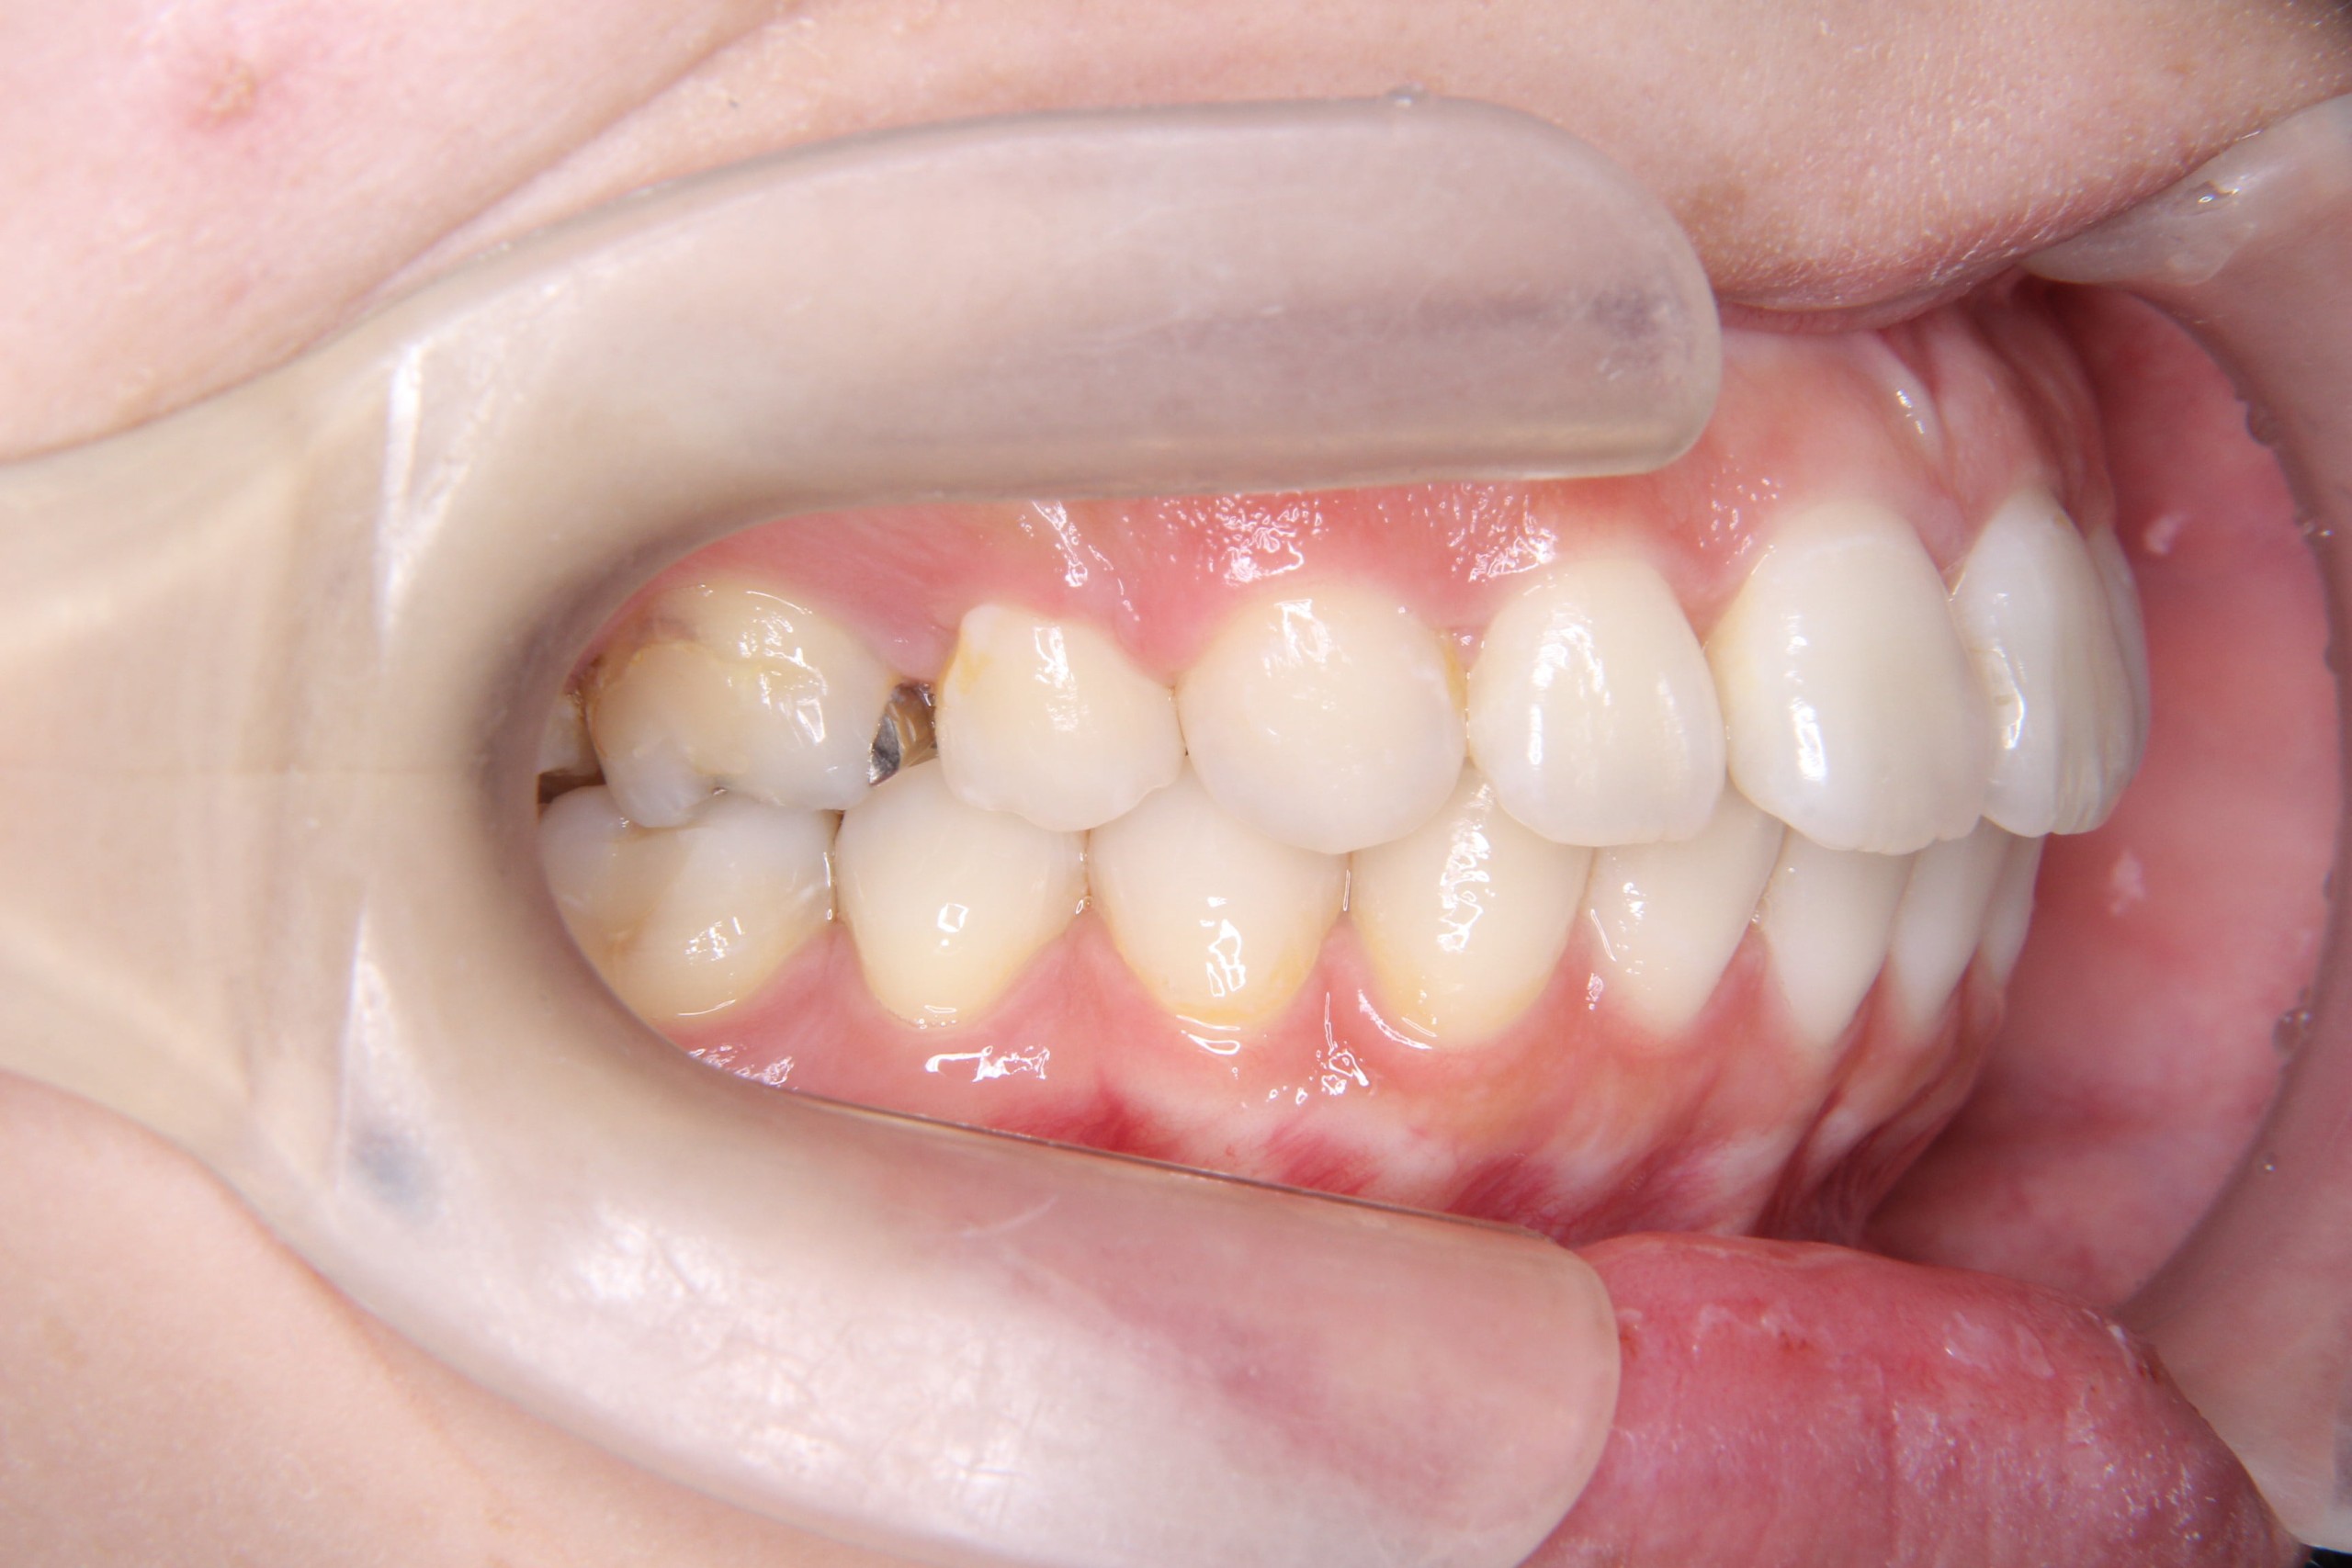

出っ歯を治したい

年齢層 20代

性別 男性

主訴 【主訴】出っ歯を治したい 【診断・症状】上下凸凹、出っ歯(上顎前突)

治療費用 検査・診断:38,500-/裏側矯正治療:1,397,000-(※全て税込)

治療期間 約1年半(20回)

抜歯 有(上4,4のみ)

矯正の装置 裏側矯正(舌側矯正)

副作用、リスク 歯肉退縮,歯根吸収,疼痛,咬合の違和感,装置の違和感,虫歯,歯肉炎

case15_出っ歯_before

Before

case15_出っ歯_after

After